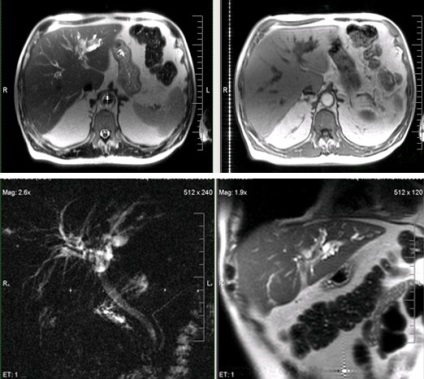

MRI képalkotó hepatocelluláris adenoma a máj

Primer májrák a leggyakoribb rosszindulatú körében ez a parenchymás szerv.

A kialakulásának kockázata hepatocelluláris karcinóma magas Májcirrhozisban, hepatitis B és haemochromatosis.

Megkülönböztetni csomópontok több csomópontos és diffúz formája.

Inváziójára a portál és máj vénák.

Klinikailag tompa fájdalom a jobb bordaív, láz, általános gyengeség, és a későbbiekben is - sárgaság.

Hepatocelluláris rák (az US - hemangioma).